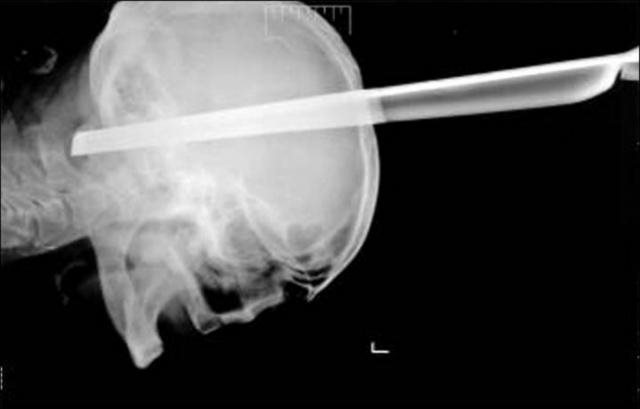

ΑΠΙΣΤΕΥΤΟ – Επέζησε, έχοντας καρφωμένο στο κεφάλι ένα μεταλλικό πόδι από σκαμπό

Ένας Σέρβος, ο οποίος ενεπλάκη σε καυγά μέσα σε νυχτερινό μαγαζί, μεταφέρθηκε στο νοσοκομείο, έχοντας σφηνωμένο μέσα στο κεφάλι του ένα μεταλλικό πόδι από σκαμπό. Οι γιατροί που αντιμετώπισαν τον σοβαρό τραυματισμό του 43χρονου άνδρα, έμειναν έκπληκτοι βλέποντας τον να αναρρώνει τόσο γρήγορα.

Το μεταλλικό αντικείμενο είχε εισχωρήσει 11 εκατοστά, στο εσωτερικό του κρανίου του, κάνοντας τους περισσότερους γιατρούς να πιστεύουν πως ο τραυματίας δεν θα κατάφερνε να κρατηθεί στη ζωή.